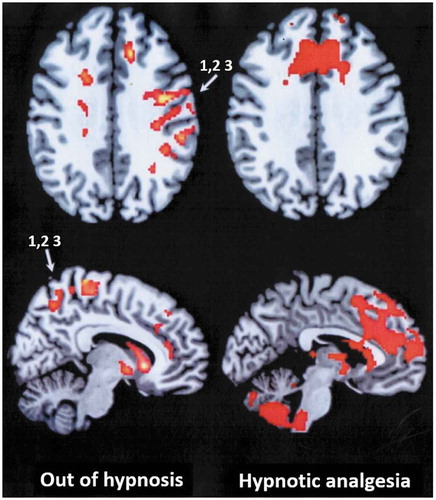

Researchers in Italy found that hypnotic-focused analgesia may prevent painful stimuli from reaching sensory cortex in the brains of highly hypnotizable people. https://www.tandfonline.com/doi/full/10.1080/00207144.2020.1685331?scroll=top&needAccess=true …

#hypnosis#analgesia#mechanisms#fMRI pic.twitter.com/m2NQll7NkR